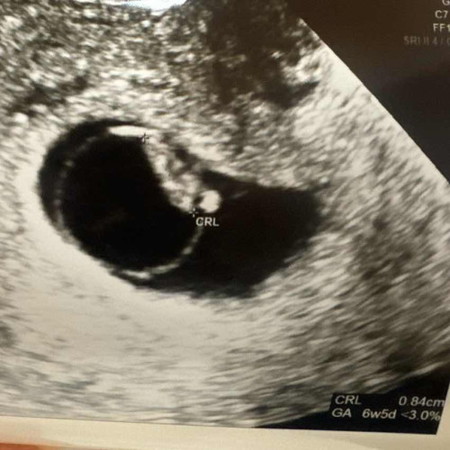

6-9 weeks ซาวเจอตัวอ่อน แต่ไม่พบหัวใจ มีหวังไหมคะ

วันนี้ไปซาวมา นับตามแอพคือ 9 วีค แต่ตามขนาดคือ 6 วีค ถ้าเจอตัวอ่อนเท่านี้ แล้วไม่เจอหัวใจ เราพอมีความหวังไหม เคยแท้งมาแล้ว ครั้งนี้ไม่อยากแท้งอีกแล้ว